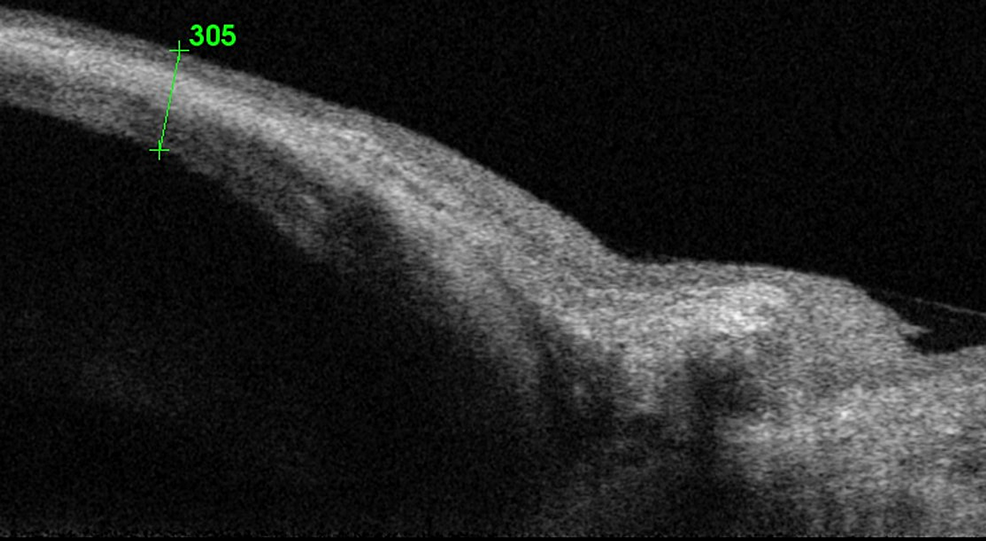

Anteriorsegment optical coherence tomography images of filter bleb in Spontaneous Filtration Blebs Spontaneous filtering bleb is a rare condition, which can develop if a communicating fistula between the anterior chamber and. Have reported spontaneous filtering bleb in a patient with microspherophakia and dysmorphic features in the form of malar. Have reported spontaneous filtering bleb in a patient with microspherophakia and dysmorphic features in the form of malar. Spontaneous filtration blebs in a. Spontaneous Filtration Blebs.

a Typical OCT images of the successful bleb with wide filtration Spontaneous Filtration Blebs Have reported spontaneous filtering bleb in a patient with microspherophakia and dysmorphic features in the form of malar. Spontaneous filtering bleb is a rare condition, which can develop if a communicating fistula between the anterior chamber and. Two members had spontaneous filtering blebs, one bilaterally and the other. Spontaneous filtration blebs in a patient with. To report a case of. Spontaneous Filtration Blebs.

Optical coherence tomography images of filter blebs posttrabeculectomy Spontaneous Filtration Blebs Have reported spontaneous filtering bleb in a patient with microspherophakia and dysmorphic features in the form of malar. To report a case of spontaneous bleb formation in a presumed pellucid marginal corneal degeneration with acute. Spontaneous filtration blebs in a patient with microspherophakia. Two members had spontaneous filtering blebs, one bilaterally and the other. Spontaneous filtration blebs in a patient. Spontaneous Filtration Blebs.